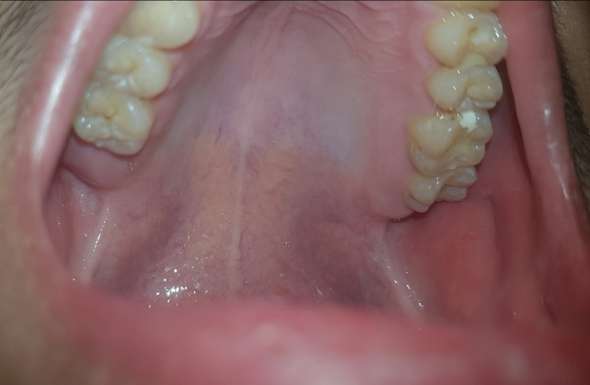

Karies weisse flecken entfernen. Doch ist das Karies?. Weiße Flecken auf den Zähnen können ein erstes Anzeichen für Karies sein Erfahren Sie hier mehr über die Symptome bei Karies Zahnbelag (Plaque) entsteht ständig neu – auch schon kurz nach dem Zähneputzen. Weiße Flecken auf den Zähnen können aber nicht nur ein ästhetisches, sondern auch ein medizinisches Problem sein und die Gesundheit Ihrer Zähne beeinträchtigen In den folgenden Absätzen erfahren Sie, worum es sich bei den weißen Flecken auf Ihren Zähnen handeln könnte, was Sie dagegen unternehmen können und wie Sie in Zukunft.

Beginnende Karies, also eine zunächst unsichtbare, oberflächliche Entmineralisierung des Zahnschmelzes, lässt sich durch Fluoride in der Zahnpasta rückgängig machen Im weiteren Kariesverlauf unterscheiden Experten vier Stufen Schreitet die Entmineralisierung des Zahnschmelzes weiter voran, entstehen weiße Flecken auf den Zähnen. Die häufigste Ursache für weiße Flecken auf den Zähnen ist eine Demineralisation des Zahnschmelzes Diese Form der Aufhellung ist das Anfangsstadium der Karies Besonders die Träger von festen Zahnspangen entwickeln unter den aufgeklebten Brackets weiße Flecken, da der Zahnschmelz unter dem Kleber Mineralien verliert Aber auch ohne Zahnspange kann der Zahnschmelz angegriffen werden und. Karies im Frühstadium Außerdem können weiße Flecken über die Entmineralisierung von Zahnschmelz.

Wir erklären, wie weiße Flecken entstehen und wie man sie behandelt Ursache für weiße Flecken Das Zusammenspiel von Fluoridtabletten, fluoridhaltiger Zahnpasta und Fluoridsalz kann zu einer Fluorose führen Das Risiko für Patienten eine Fluorose zu bekommen ist individuell verschieden. Karies heilen – mit hochwertigen Füllmaterialien Erste Anzeichen sind weiße Flecken auf den Zähnen, aber auch unangenehme Zahnschmerzen wie Hitze und Kälteempfindlichkeit Beugen Sie einer weiteren Entzündung des Zahnnervs vor und kommen Sie bei einem Verdacht schnell in unsere Praxis. Weiße Flecken können ein Hinweis auf Karies in der Anfangsphase sein Der sogenannte initiale Karies entzieht dem Zahn Kalk & andere Mineralstoffe und sorgt für einen veränderten Farbton (Schmelzflecken).

Weiße Flecken auf den Zähnen Karies droht Beginnende Karies ist heilbar, wird aber nur vom Experten rechtzeitig erkannt Die Behandlung setzt an den Ursachen an und ist vollkommen schmerzfrei Zahnärzte verstehen darunter kreidigweiße Veränderungen im Zahnschmelz, die das Frühstadium einer Karies signalisieren. Karies und weiße flecken Hallo, Wie gesagt besser den Zahn entfernen Bitte ein Röntgenbild machen lassen und dann möglicherweise bei einem Kinderzahnarzt über die Möglichkeiten einer Sedierung beraten lassen Leider haben Kinder, die an einer Stelle ein großes Loch haben auch an anderen Zähnen bereits eine versteckte Karies. Weisse Flecken auf den Zähnen können ein erstes Anzeichen für Karies sein Erfahren Sie hier mehr über die Symptome bei Karies Schmerzempfindliche Zähne können ein Anzeichen für Zahnschmelzabbau sein Mehr erfahren Zahnbelag kann nur mechanisch, das heisst mit Zahnbürste und Zahnseide, entfernt werden.